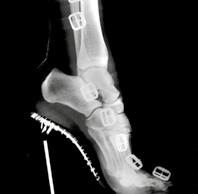

Das liegt auch daran, dass Medartis sein Produkt portfolio kontinuierlich ausbaut. Schon 2010 ist man mit der Fusschirurgie in das Geschäftsfeld der unteren Extremitäten eingestiegen. In den oberen Extremitäten kommen Implantatsysteme für den Ellbogen hinzu, etwas später auch solche für die Schulter. Das Ellbogensystem wurde von einem Designteam aus zehn Ärztinnen und Ärzten mitentwickelt und von den Chirurgen Prof. Dr. Lars Müller, Dr. Klaus Burkhart und Dr. William Geissler geprägt. Ergänzt werden diese Systeme von einer neuen Technologie: der patentrechtlich geschütz ten SpeedTip-Schraube (Seite 56 – 57). Deren selbstschneidendes Gewinde ist rasiermesser scharf, sodass die Ärzteschaft auf das Vorbohren des Knochens verzichten kann. Das spart Zeit im Operationssaal.

2008 SpeedTip

Aus der Patentschrift von 2006: die SpeedTip-Schraube von unten aus betrachtet mit dreieckig zulaufender Schraubenspitze.

Nach der Spitze wird die Schraube etwas schmaler, in Richtung Schraubenkopf verbreitert sie sich wieder. Diese Form garantiert minimale Reibung im Knochengewebe.

Achtung, scharf!

werden musste. Für die Fixation des Ober- und Unterkiefers nach einem Kieferbruch möchte die Ärzteschaft selbstboh rende und selbstschnei dende Schrauben ver wenden, um aufwendige Drahtligaturen zu vermei den. Damit muss sie den Knochen des Patienten weder vorbohren noch

ein Gewinde schneiden. Doch die stählernen IMF-Schrauben (inter maxilläre Fixation) auf dem Markt haben einen entscheidenden Nach teil: Bei zu grossem Drehmoment brechen sie – ein Alptraum im Operationssaal!

Kieferchirurginnen und -chirurgen wenden sich mit einem ungelösten Problem an die Industrie, Medartis antwortet mit der wohl schärfsten Schraube der Welt.

Kanülierte, also hohle Kompressionsschraube.

M edartis vertraut das Projekt ihrem Ent wickler Dirk Thiel an, der schon die TriLock-Tech nologie mit seinen Ideen geprägt hat. Nun soll Thiel eine selbstbohren de und selbstschneiden de Schraube entwickeln, die unzerbrechlich ist.

Was diese Aufgabe zu sätzlich knifflig macht: Die Schraube muss aus Titan hergestellt werden, weil dieses biokompa tibler ist als Stahl – aber leider auch weicher. Es gibt nur eine Option: Statt den Härtegrad der Schraube zu erhöhen, muss Thiel das Dreh moment senken. Die Schraube muss sich mit möglichst geringer Kraft in den Knochen drehen lassen, sodass keine Gefahr besteht, dass sie abbricht.

Eine Voraussetzung dafür ist, dass das Schraubengewinde rasiermesserscharf ist. Das ist vor allem für den

Prototypenbau eine Herausforderung, denn in der Theorie ist klar: Je dünner die Gewindespit ze, also der äusserste Teil des Gewindes, desto schärfer die Schraube. Hauchdünne Gewinde spitzen zu fertigen, setzt aber grosses Know-how voraus. Der Leiter des Prototypenbaus, Peter Scheuble, und der Fein mechaniker Alain Hasen böhler nehmen sich der Sache an, loten die Gren ze des Machbaren aus und fertigen am Ende Gewindespitzen, die zwei hundertstel Millimeter dünn sind.

Doch damit ist die Arbeit nicht getan. Trotz scharfer Gewindeflanken stellt Dirk Thiel fest:

Im Knochen nimmt die Reibung und damit das Drehmoment zu. Beim Tüfteln fällt ihm auf, dass sich die Schraube leichter eindrehen lässt, wenn sie in Richtung Schraubenkopf dünner

wird. So ist die Reibung im Knochen minimal. Nun muss Thiel das richtige Mass finden. Letztlich machen wenige zehntel Millimeter Ver jüngung der Schrauben mitte den Unterschied.

Die ungleichmässig dicke Schraube am Langdreher zu fertigen, hat ebenfalls seine Tücken – womit wieder Scheuble und Hasenböh ler ins Spiel kommen. Während Scheuble an den Wochenenden an seiner hölzernen Ve randa zimmert, kommt ihm eine Idee, wie er die neuartige Schraube optimieren könnte: mit einer dreieckigen Spitze, wie sie bei Schrauben im Holzbau üblich ist.

Tatsächlich funktioniert das Prinzip auch in der Medizinaltechnik. Die dreieckige Spitzengeo metrie bohrt, verdrängt und verdichtet das

Knochengewebe beim Eindrehen und sorgt so für erhöhte Ausreissfes tigkeit. Zudem schneidet sie den Knochen schon bei geringem Anpress druck sofort an. Das spart Kraft und Zeit im Operationssaal.

2008 kommt die erste SpeedTip-Schraube auf den Markt. Sie wird zum Erfolg, auch weil Medartis sie geschickt vermarktet. 2011 folgen die kanülierten Kom pressionsschrauben SpeedTip 2.2 und 3.0 für die Anwendung in den Extremitäten.

In den Kliniken ist seither Ruhe eingekehrt. Und wenn Medartis doch eine Rückmeldung zur SpeedTip-Schraube bekommt, ist es immer dieselbe: «Die geht rein wie in Butter.»

Kompressionsschrauben mit verschiedenen Durchmessern für die Anwendung in den Extremitäten.